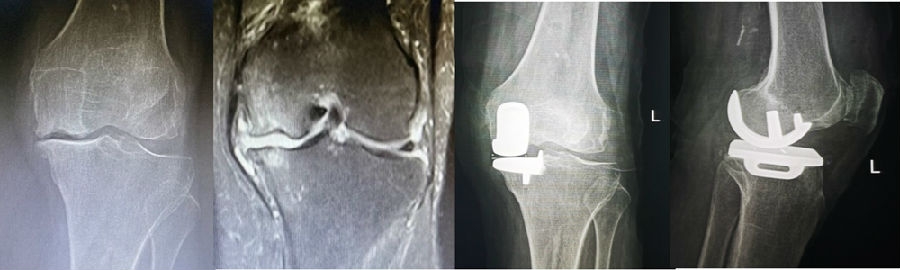

病例1:女,61岁,右膝关节诊断为Koshino Ⅲ期SONK,行右膝内侧单髁手术治疗。

(4)Koshino Ⅳ期SONK

由于存在继发退行性改变,一般不建议单纯行膝关节镜+自体骨软骨移植术。需在考虑5个因素的基础上兼顾患者年龄、性别和活跃程度,分别选择膝关节镜+HTO术+微骨折术、膝关节镜+HTO+坏死区病灶刮除+自体植骨术或单髁置换术。对于合并症状性髌股关节炎、外翻畸形、坏死区范围大影响单髁假体稳定性等的Koshino Ⅳ期膝关节股骨内侧髁SONK,采用全膝关节置换术。

病例1:男,64岁,主诉左膝关节内侧疼痛6年余。MR提示骨坏死区占比为33.28%,矢状位病变区域前后径为26.42mm,半月板相对突出百分比(RPE)31.78%,同时存在胫骨侧来源的下肢内翻畸形(MPTA83°),关节线会聚角2°。

行关节镜检查+软骨摘除+微骨折+HTO术,术后随访2年恢复良好,活动自如,行走时无左膝关节疼痛不适。

病例2:女,81岁,行内侧单髁手术治疗,术后恢复良好。